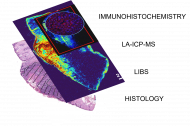

Získali jsme sadu vzorků různých tumorů kůže, ať už se jedná o maligní nádory – melanomy, bazocelulární karcinomy, spinocelulární karcinomy – nebo benigní (nezhoubné) nádory. Pomocí čtyř technik (LIBS, LA-ICP-MS, imunohistochemie, klasická histopatologie) je analyzujeme a snažíme se o korelativní zobrazování. Výsledkem projektu má být algoritmus, který by byl „natrénovaný“ z našich vzorků a byl by schopen říct – tohle je oblast tumoru, tohle už oblast tumoru není. Ale je to ještě hodně vzdálená budoucnost.